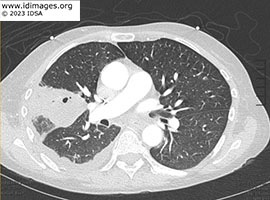

A chest radiography (posterior-anterior and lateral) demonstrated a right upper lobe pneumonia (Figure 1). Computed tomography (CT) of the chest (Figure 2) with contrast demonstrated a mass like consolidative opacity within the right upper lobe containing small foci of gas, concerning for pulmonary abscess. Scattered subcentimeter pulmonary nodules, some are stable but the majority are new.

- Figure 2: Computed tomography scan of chest with contrast.